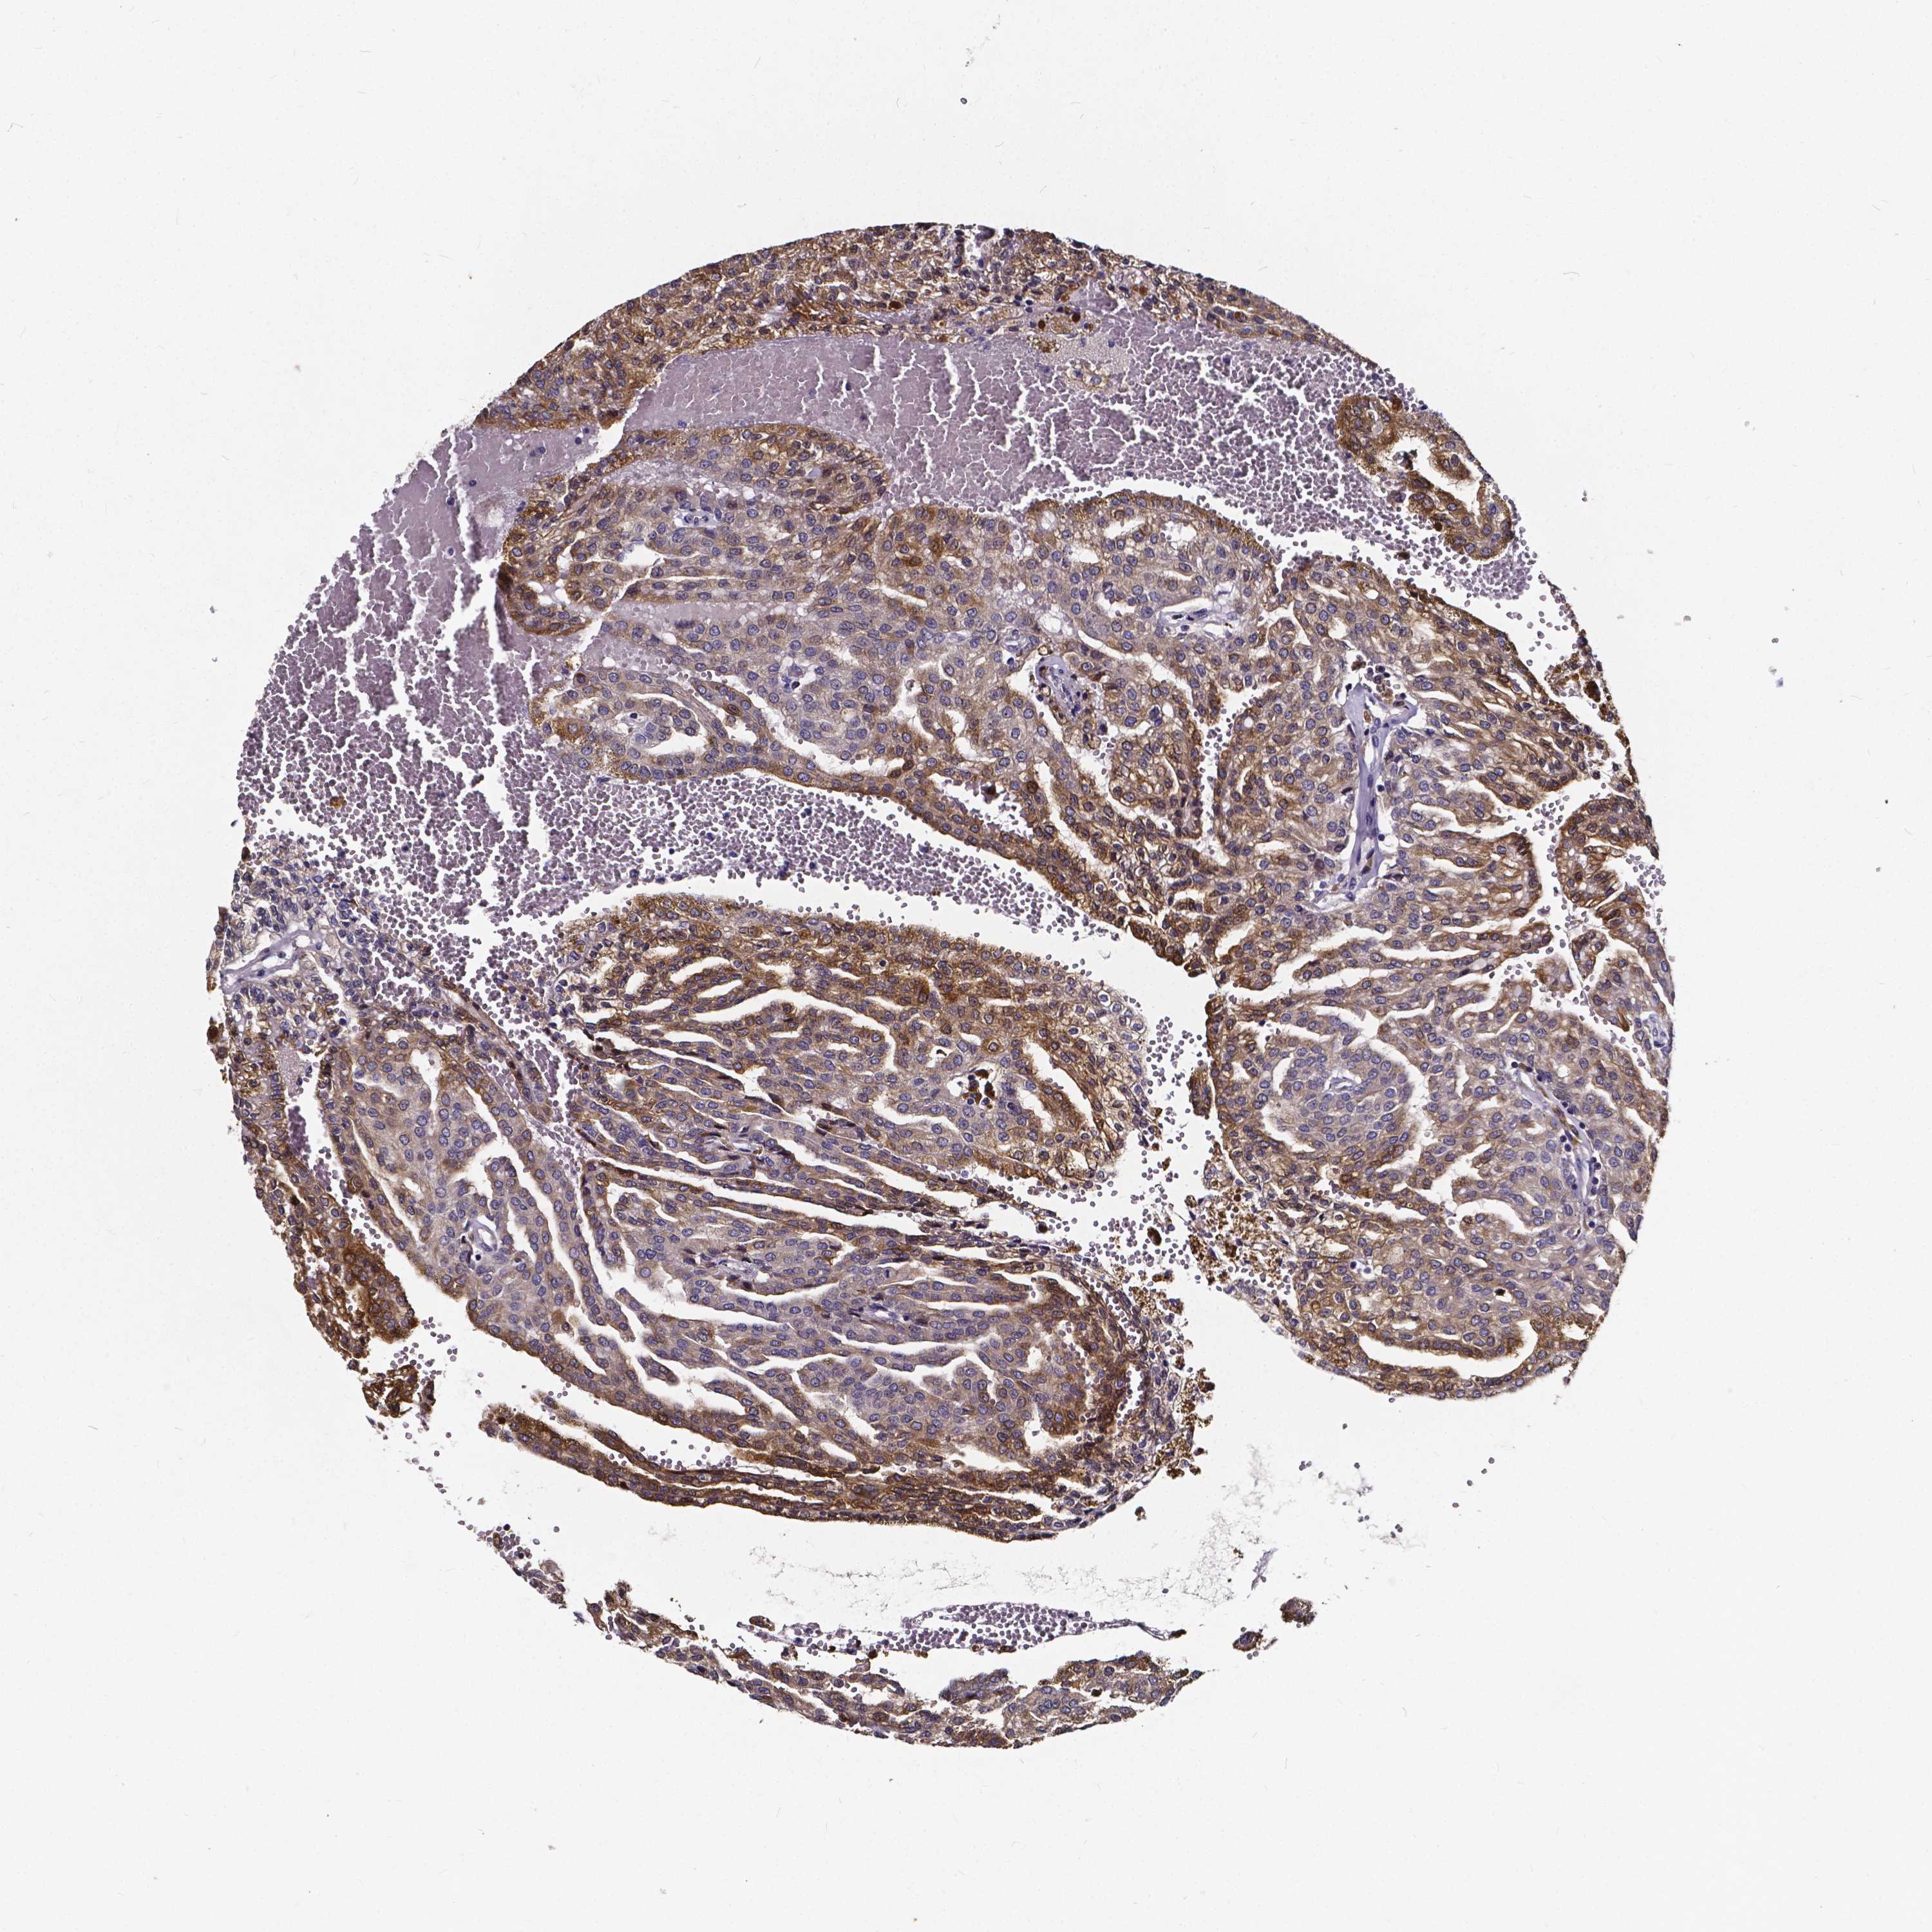

CANCER RENAL CANCER Show tissue menu

Renal cancer

Kidney renal papillary cell carcinoma